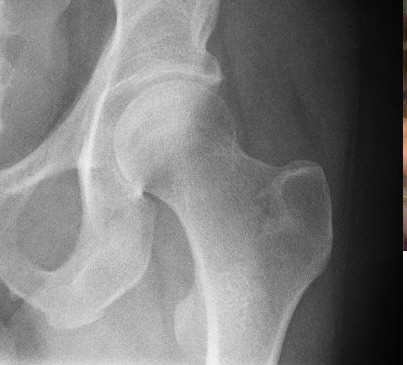

Monitoring results of total hip replacement

hippyIn hip replacement surgery, an important technical factor is the inclination angle of the acetabular component. Variations from the target angle can lead to increased amount of wear and poorer outcomes after surgery. Therefore, researchers used time-weighted control charts in Minitab, such as CUSUM, EWMA, and MA charts, to monitor the acetabular inclination angle in the postoperative radiographs of patients who underwent hip replacement surgery.  The control charts demonstrated that the surgical process, in relation to the angle achieved, was stable and in control. The researchers noted that the time-weighed control charts helped them make a "faster visual decision." Biomed Research International 2015; ID 199610.